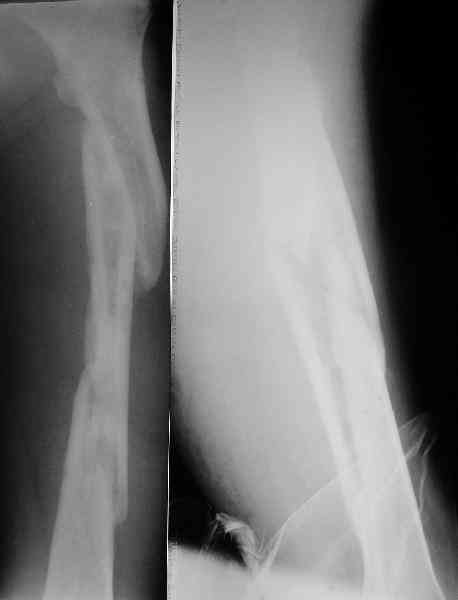

Уважаемые коллеги! Пришел на консультацию вот такой больной (первые 3-и рисунка). Травма автодорожная, апрель 2006г. Лечился консервативно, вытяжение и гипс. Через пять месяцев стал ходить. Укорочение бедра 6 см. 26 февраля 2007г. оступился, упал. Прооперирован в г.Баку - наложен стержневой аппарат. Ходит с костылями, наступая на левую ногу. Мы попросили что нибудь из ранних снимков. Принес рентгенограммы перелома (рис. 4,5). Посмотрели, наснимали сами (рис. 6-10). Похоже, что нет сращения нигде. Хотелось - бы обсудить следующие вопросы:1. дальнейшая тактика - реостеосинтез или подождать (ослабить аппарат, дать нагрузку и т.д.)?2. если реостеосинтез - то чем и как? Юрий Алексеевич Булахтин